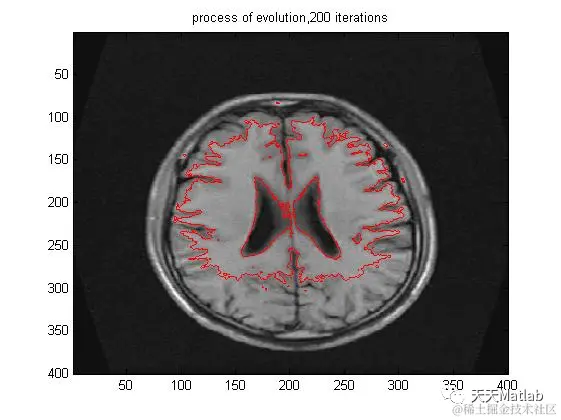

​3 仿真结果

title(['process of evolution,',iterNum]);